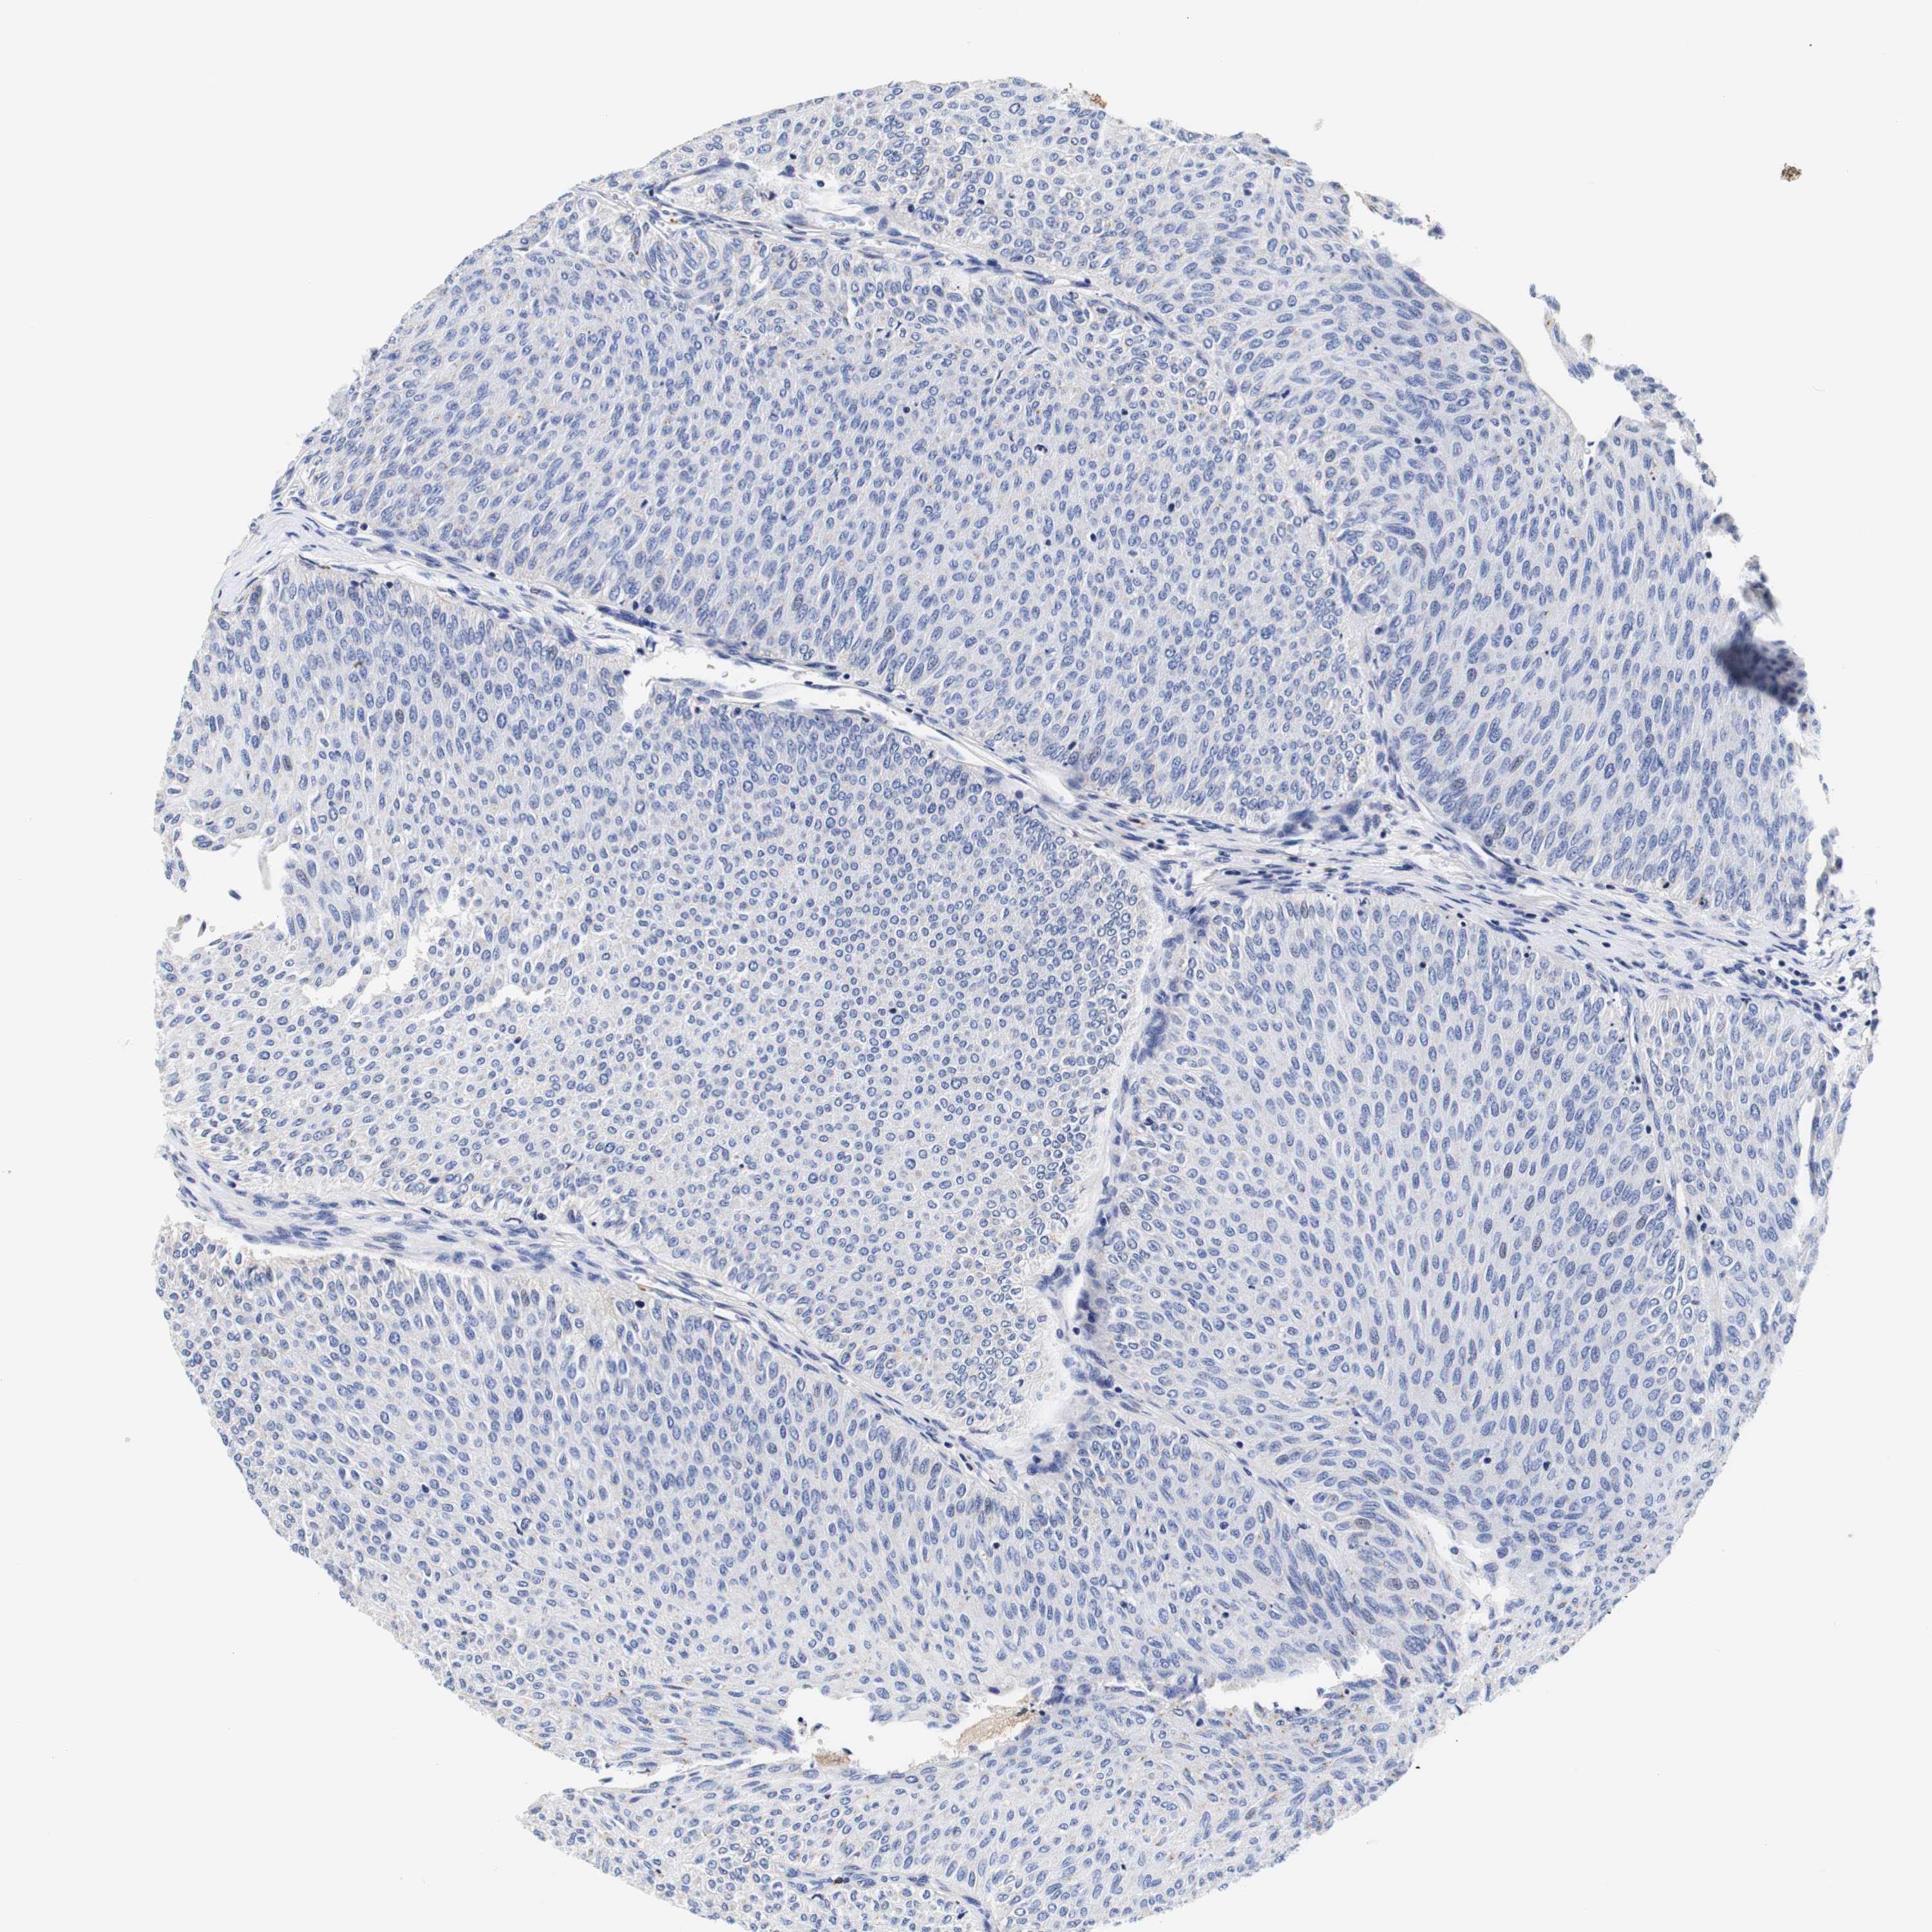

UROTHELIAL CANCER - Protein expressioni

A mouse-over function shows sample information and annotation data. Click on an image to view it in a full screen mode. Samples can be filtered based on level of antibody staining by selecting one or several of the following categories: high, medium, low and not detected. The assay and annotation is described here.

Antibody stainingi

Antibody staining in the annotated cell types in the current human tissue is reported as not detected, low, medium, or high, based on conventional immunohistochemistry profiling in selected tissues. This score is based on the combination of the staining intensity and fraction of stained cells.

Each image is clickable and will lead to virtual microscopy that enables deeper exploration of all samples and also displays staining intensity scores, fraction scores and subcellular localization as well as patient and tissue information for each sample.

Antibody HPA011753

Urothelial carcinoma, Low grade

Urothelial carcinoma, High grade